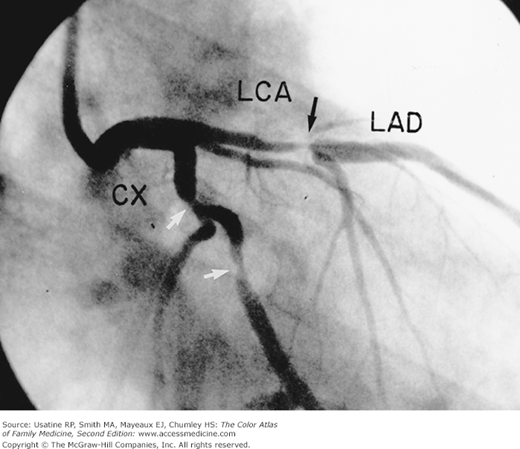

Хроническая окклюзия артерий: причины, симптомы и лечение